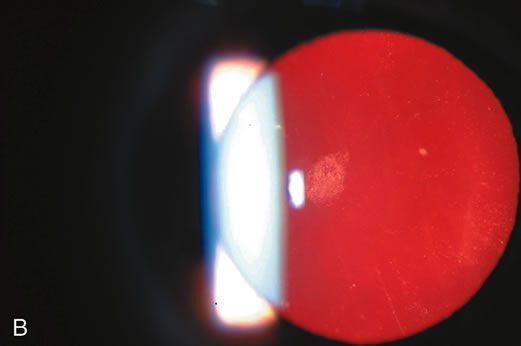

Fig. 3. Posterior subcapsular cataract (PSC) using (A) direct illumination and (B) retroillumination. PSCs usually start centrally and extend toward

the periphery. For this reason, they interfere with visual function, causing

glare disability early.

Fig. 3. Posterior subcapsular cataract (PSC) using (A) direct illumination and (B) retroillumination. PSCs usually start centrally and extend toward

the periphery. For this reason, they interfere with visual function, causing

glare disability early.

beams. Retroillumination uses the light reflected from the fundus to highlight

opacities. This is very useful in examining cortical and posterior subcapsular

cataracts (Figs. 1, 3, 7, and 8). However, some cortical water clefts and early posterior subcapsular

opacities may not be easily seen with retroillumination if they are

not dense enough to cast shadows or only refract the retroilluminate

light; these can be best seen with the broad beam. Using retroillumination

on nuclear cataracts does not give much information because these

usually do not cast shadows. However, as seen in Figure 2B, a change in the refractive index can be seen toward the center. Usually, the